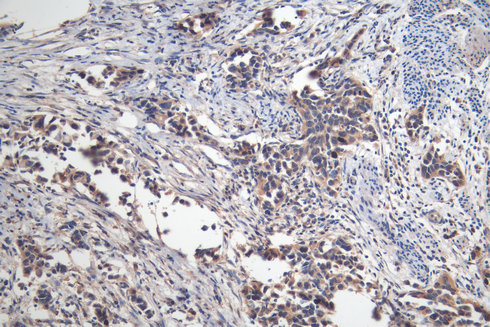

CLEAVED PARP是PARP(Poly ADP-ribose polymerase)家族成員之一。PARP細(xì)胞核酶,在細(xì)胞凋亡以及DNA修復(fù)等生物學(xué)過程中發(fā)揮了關(guān)鍵的